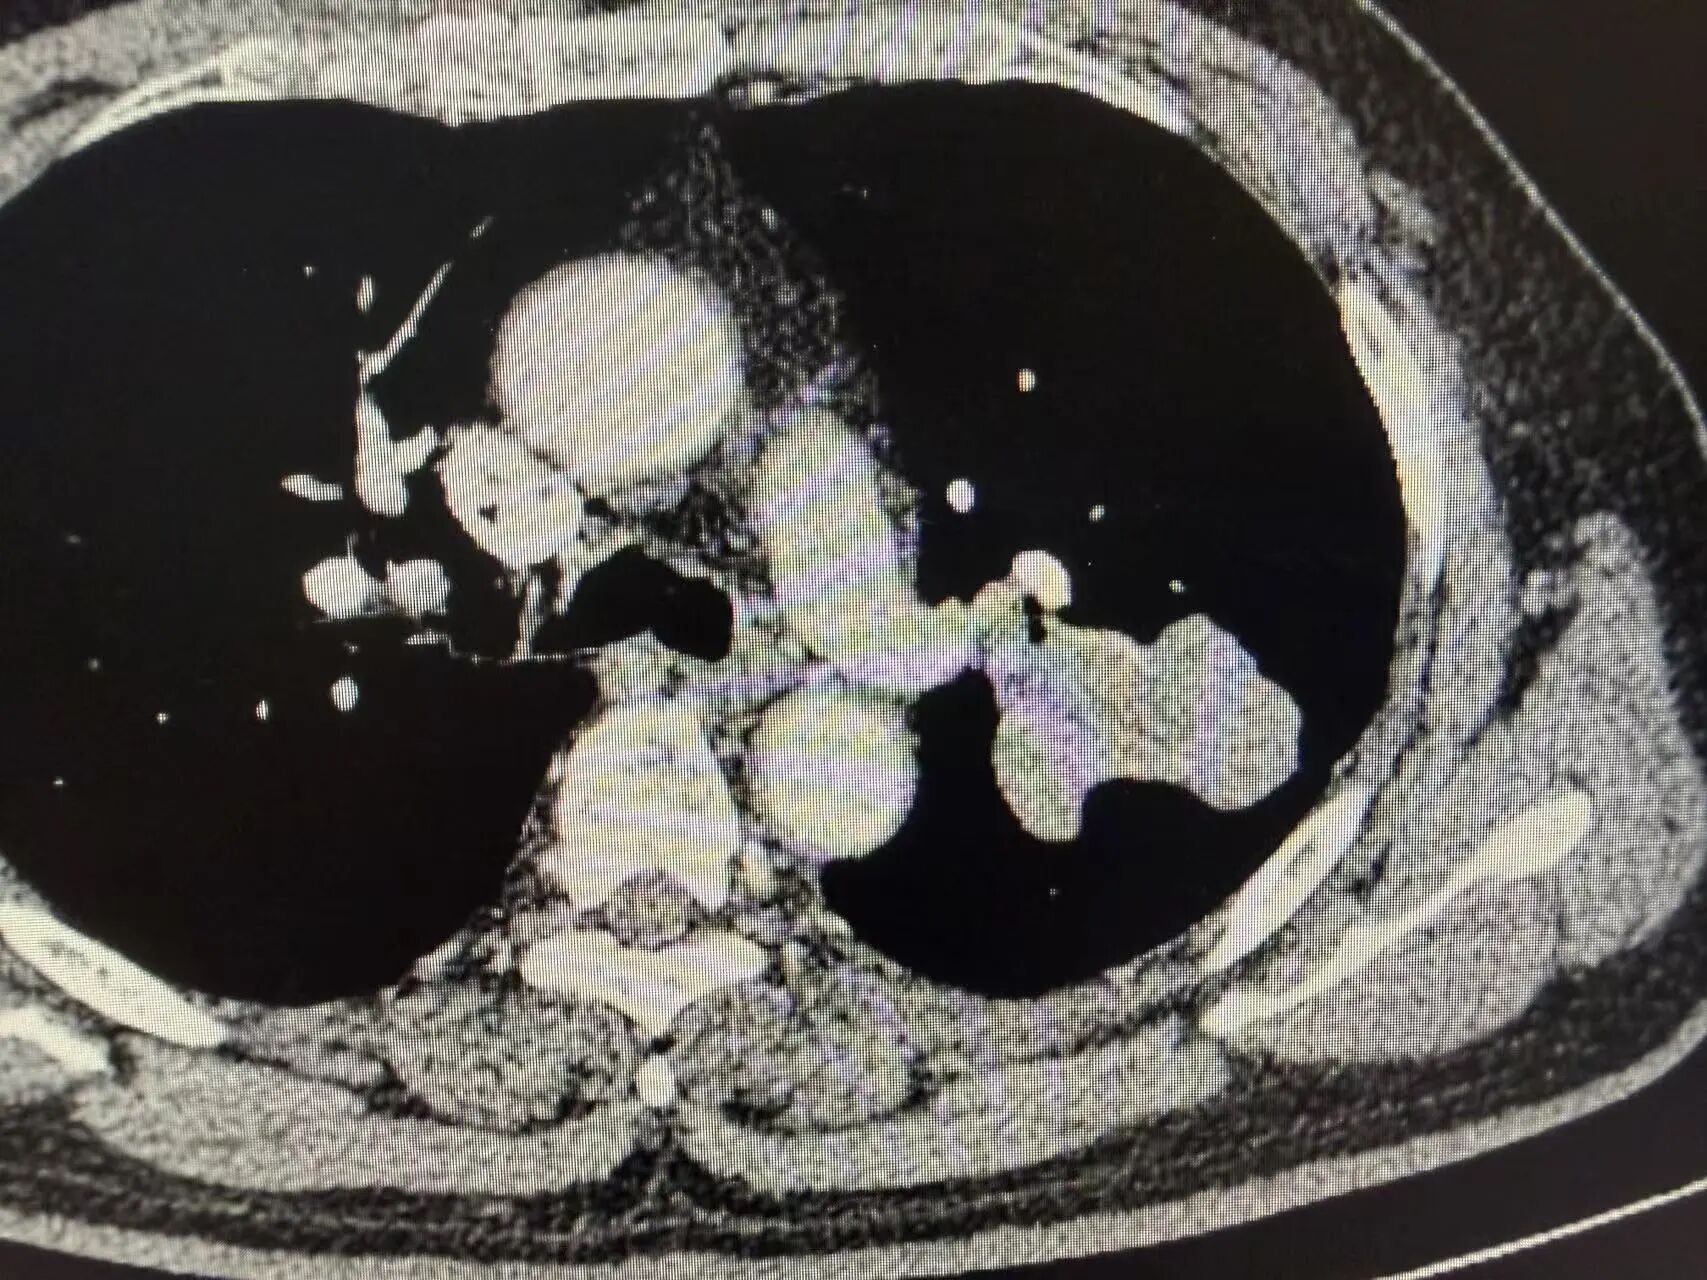

复查胸部CT显示:原左上肺肿瘤病灶显著缩小,肿大的肺门淋巴结基本恢复正常大小,肿瘤评估达到显著临床缓解,手术时机成熟。

新辅助治疗后CT影像